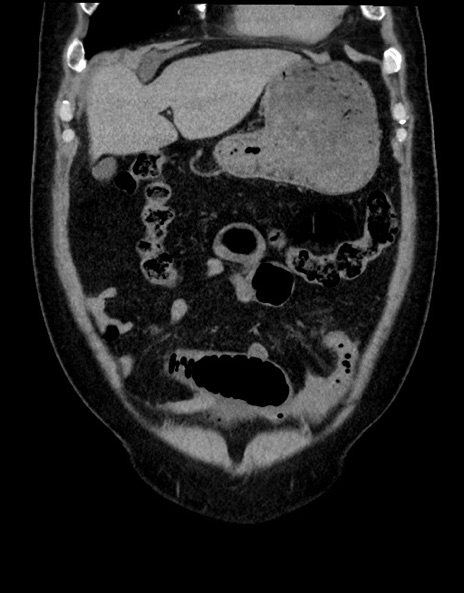

症例15(冠状断像)

【症例】70歳代男性

【主訴】腹痛

【現病歴】今朝から腹痛あり。全体的に痛い。特に左上の方。排ガスが今日はない。冷や汗が出る。

【既往歴】直腸癌術後

【身体所見】左側腹部〜上腹部に圧痛あり。腹膜刺激症状明らかなではない。軽度反跳痛。左下腹部に術後瘢痕あり。

【データ】WBC 7700、CRP 0.02